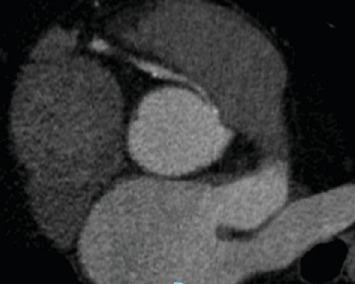

摘要冠状动脉异常起源是一种罕见的先天性心脏缺陷。随着心脏计算机断层扫描和磁共振成像技术的应用,冠状动脉异常的检测可能会增加。一旦发现异常冠状动脉,手术干预的建议取决于患者的症状、应激成像上是否存在诱导性缺血以及高危解剖特征。77岁男性,有高血压、高脂血症、慢性肾脏病III期和中度主动脉狭窄病史,表现为非st段抬高型心肌梗死,横断面成像发现右冠状动脉主动脉起源异常。他的主动脉狭窄也从中度发展到重度,目前尚不清楚他的心肌梗死是否完全归因于主动脉深度狭窄背景下的供需差异,或者他异常的冠状动脉解剖结构是否可能是导致他出现这种情况的罪魁祸首。一个多学科的心脏小组决定进行经导管主动脉瓣置换术,如果他的心绞痛症状在瓣膜置换术后持续存在,然后重新对他的右冠状动脉异常进行手术干预。

Anomalous aortic origin of a coronary artery is a rare congenital heart defect. The detection of anomalous coronary arteries is likely to increase with increased availability and application of cardiac computed tomography and magnetic resonance imaging. Once detected, the recommendation for surgical intervention on anomalous coronary arteries depends upon patient symptoms, the presence or absence of inducible ischemia on stress imaging, and high-risk anatomic features. A 77-year-old man with a history of hypertension, hyperlipidemia, chronic kidney disease Stage III, and moderate aortic stenosis presented with a non-ST-elevation myocardial infarction and was found to have an anomalous aortic origin of the right coronary artery on cross-sectional imaging. His aortic stenosis had also progressed from moderate to severe, and it was not clear whether his myocardial infarction could be exclusively attributed to a supply-demand disparity within the context of profound aortic stenosis or if his aberrant coronary anatomy could be implicated as the culprit for his presentation. A multidisciplinary heart team decided to proceed with a transcatheter aortic valve replacement and then readdress surgical intervention on his anomalous right coronary artery if his anginal symptoms persisted following valve replacement.